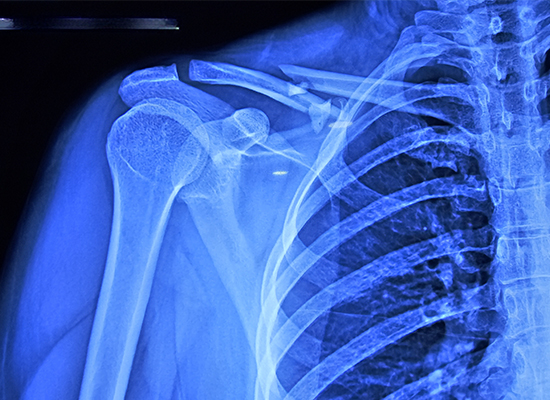

The patient, a 34-year-old female, suffered a right clavicle fracture classified as Allman Type 1, meaning it was a midshaft fracture. This type of injury can often lead to complications if not treated correctly. After examining the patient’s condition and reviewing her imaging results, Dr. Pedro recommended an open reduction and internal fixation (ORIF) procedure with an S-clavicle locking plate.

The 34-year-old female patient had an Allman Type I midshaft fracture with multiple fragments.

Because of the multi-fragmented and displaced nature of the fracture, conservative fixation could not achieve alignment, so ORIF was selected.